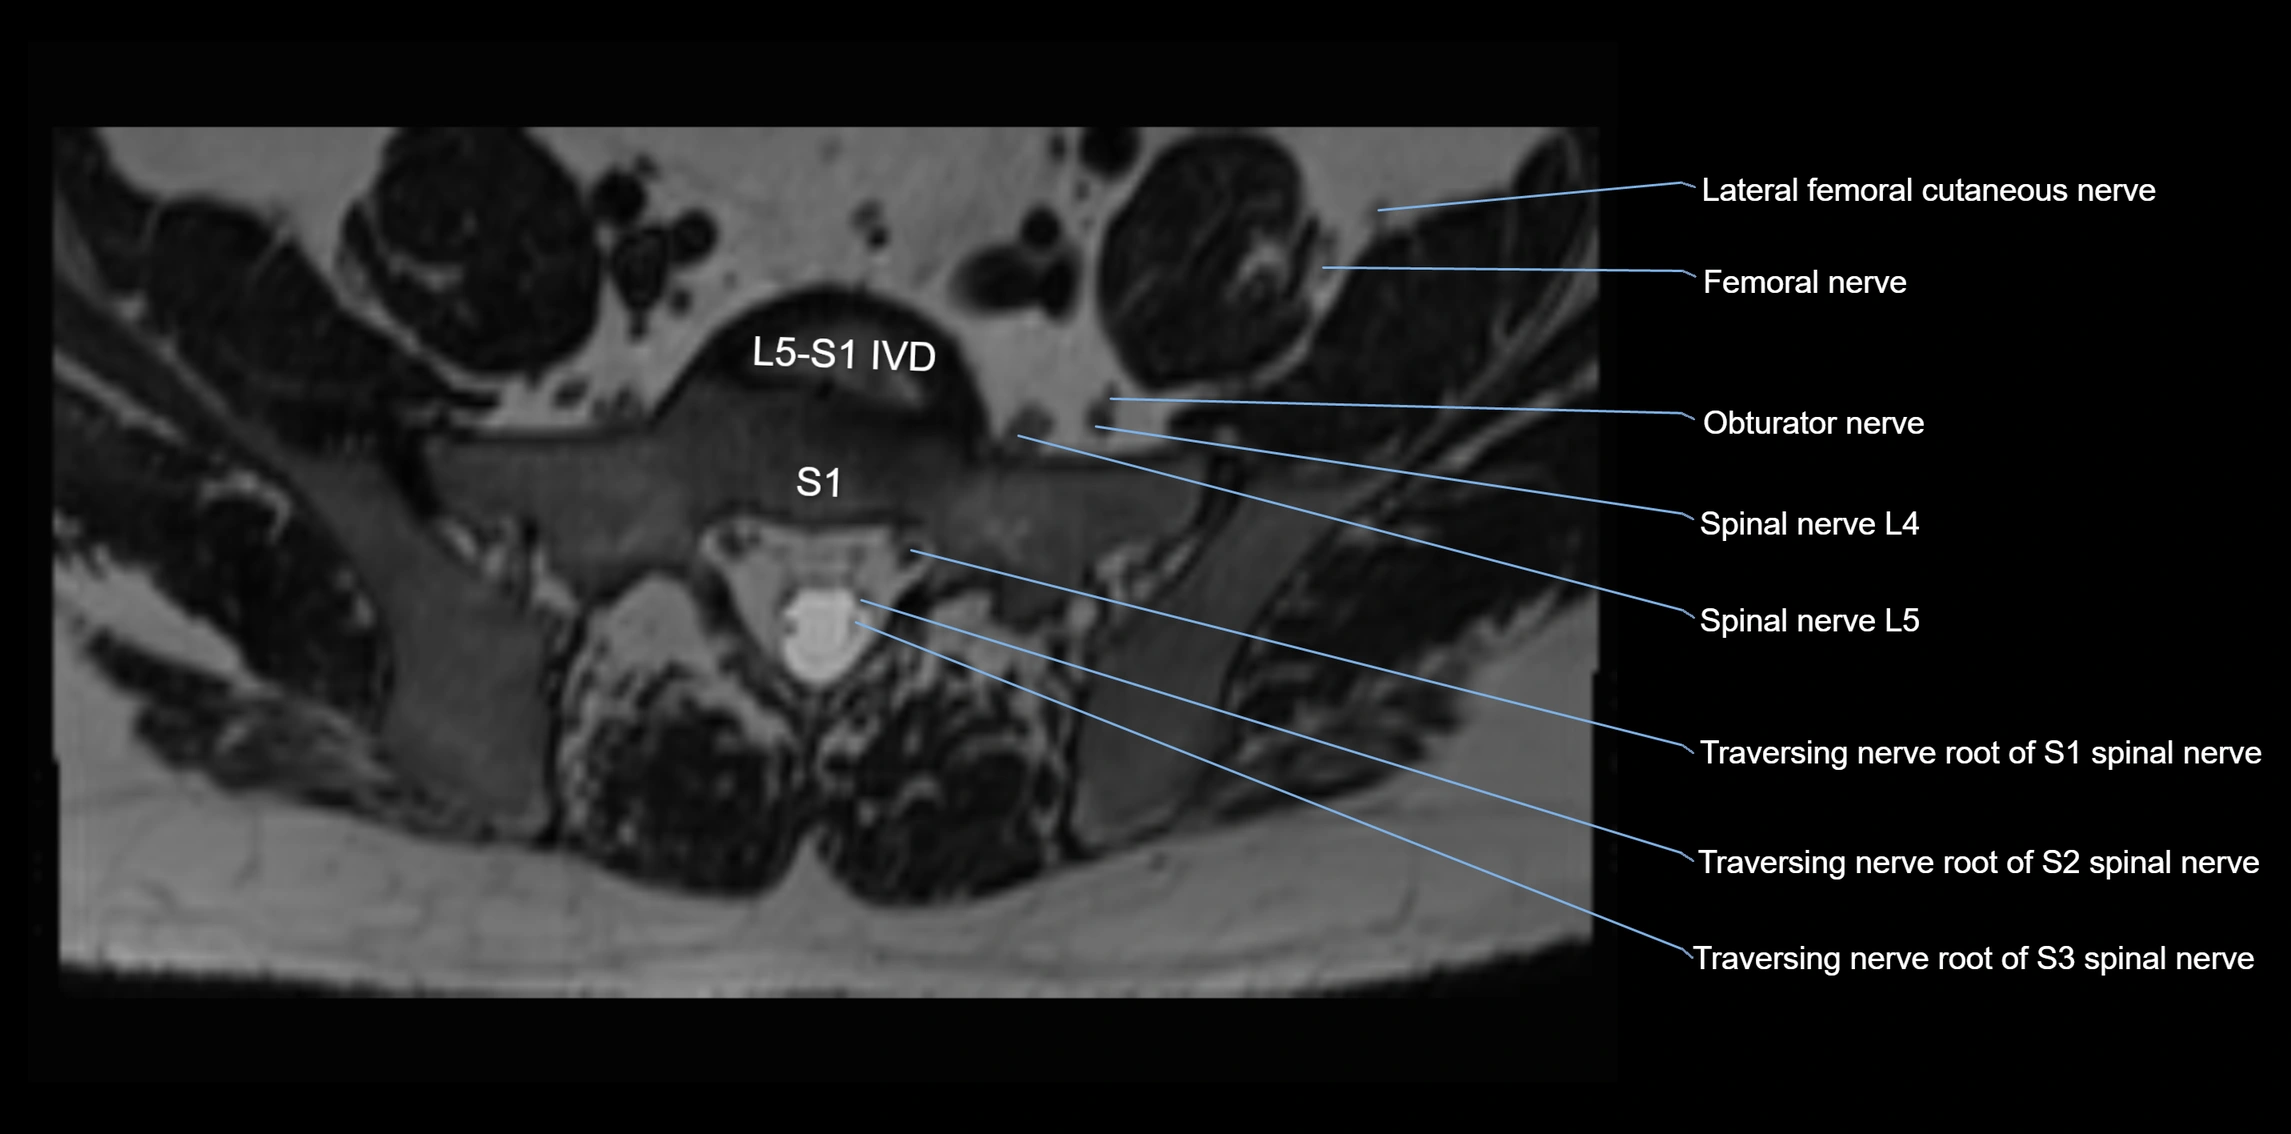

MRI Appearance

T1-weighted images:

• Nerve appears as a very thin low-to-intermediate signal intensity structure

• Surrounded by bright fat, aiding visualization

T2-weighted images:

• Nerve shows intermediate to mildly hyperintense signal compared to muscle

• Pathological involvement appears brighter

STIR (Short Tau Inversion Recovery):

• Normal nerve appears dark

• Inflamed or entrapped nerve appears bright hyperintense

T1 Fat-Sat Post-Contrast:

• Normal nerve enhances minimally

• Pathologic nerve (neuritis, entrapment, tumor infiltration) shows focal or diffuse enhancement

3D T2 SPACE / CISS:

• Nerve appears intermediate to mildly hyperintense compared to muscle

• Surrounded by bright fat or CSF, improving visualization

• Best sequence for mapping small pelvic nerves such as the anococcygeal